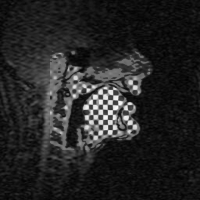

Vocal tract images are made in multiple planes during sustained speech sounds. Tagged Cine-MRI (tMRI) allows tracking of tissue points in oral structures.

![]() |

Subject saying /i/ |

| Tagged Cine-MRI (tMRI) -Planar | Tagged Cine-MRI (tMRI) -MICSR |